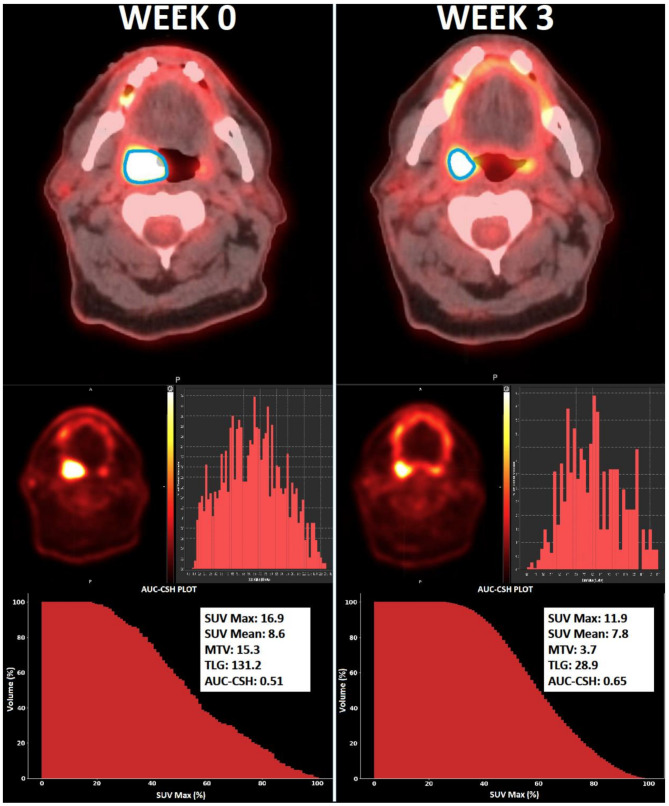

Background: This study evaluated mid-treatment changes in intra-tumoural metabolic heterogeneity and quantitative FDG-PET/CT imaging parameters and correlated the changes with treatment outcomes in oropharyngeal squamous cell cancer (OPSCC) patients. 114 patients from two independent cohorts underwent baseline and mid-treatment (week 3) FDG-PET. Standardized uptake value maximum (SUVmax), standardized uptake value mean (SUVmean), metabolic tumour volume (MTV), and total lesional glycolysis (TLG) were measured. Intra-tumoural metabolic heterogeneity was quantified as the area under a cumulative SUV-volume histogram curve (AUC-CSH). Baseline and relative change (%∆) in imaging features were correlated to locoregional recurrence free survival (LRRFS) using multivariate Cox regression analysis. Patients were stratified into three risk groups utilising ∆AUC-CSH and known prognostic features, then compared using Kaplan-Meier analysis.

Results: Median follow up was 39 months. 18% of patients developed locoregional recurrence at 2 years. A decrease in heterogeneity (∆AUC-CSH: 24%) was observed mid-treatment. There was no statistically significant difference in tumour heterogeneity (AUC-CSH) at baseline (p = 0.134) and change at week 3 (p = 0.306) between p16 positive and p16 negative patients. Baseline imaging features did not correlate to LRRFS. However, ∆MTV (aHR 1.04; 95% CI 1.03-1.06; p < 0.001) and ∆AUC-CSH (aHR 0.96; 95% CI 0.94-0.98; p = 0.004) were correlated to LRRFS. Stratification using ∆AUC-CSH and p16 status into three groups showed significant differences in LRR (2 year LRRFS 94%, 79%, 17%; log rank p < 0.001). Stratification using ∆AUC-CSH and ∆MTV into three groups showed significant differences in LRR (2 year LRRFS 93%, 70%, 17%; log rank p < 0.001).